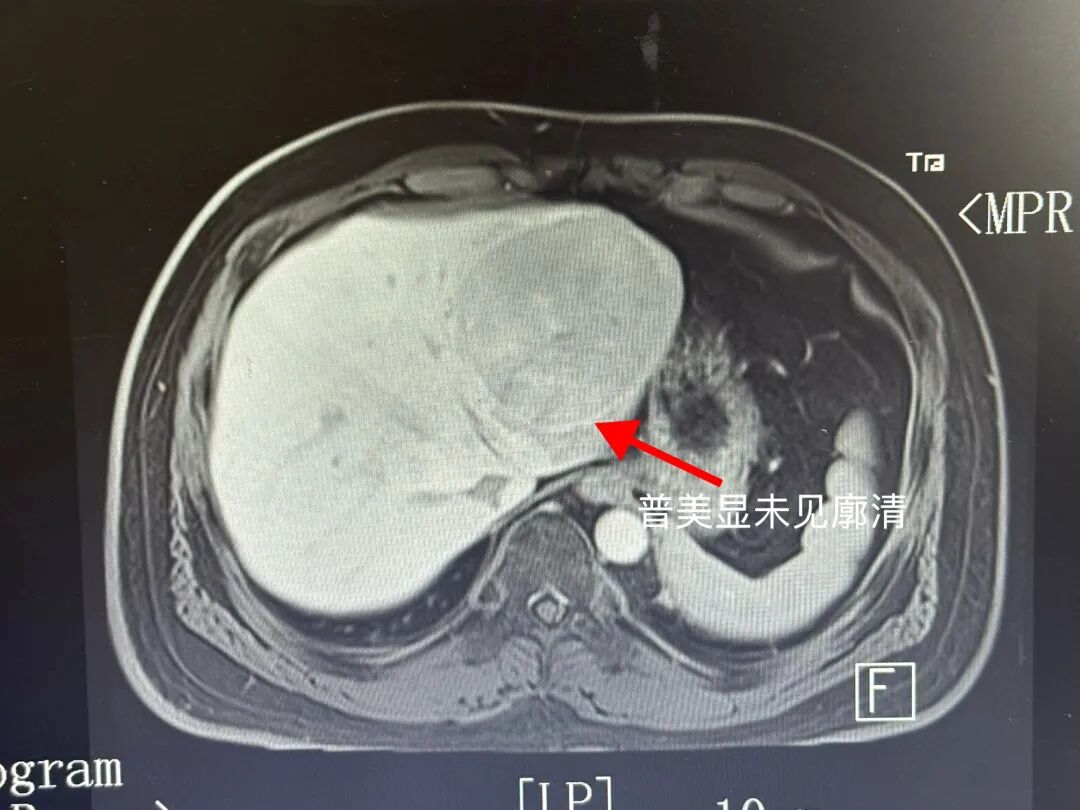

患者是30多岁男性,体检发现肝占位5月余,无

影像评估与手术规划:LHV没有显影,MHV、UFV完整,肿瘤位于矢状部左侧,P4ab完整。我的计划做左外叶可解决问题。